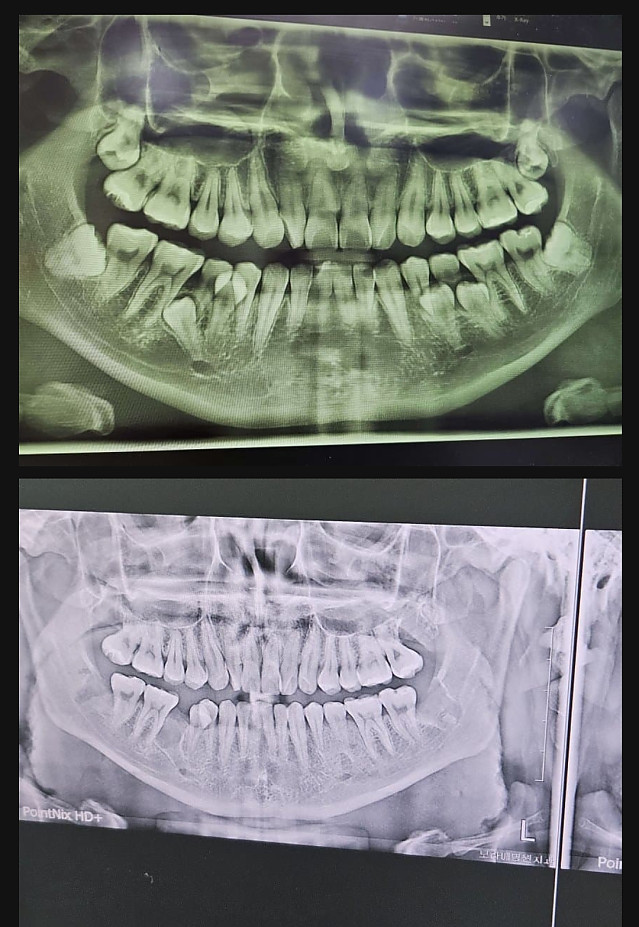

사랑니 갤러리 갤주 작성자 정보 붐붐의민족 작성 작성일 2024.10.18 11:28 컨텐츠 정보 13,968 조회 1 댓글 목록 본문 서울대병원 전신마취 수술로 정상화 완료 관련자료 링크 https://www.kaov.org/bbs/board.php?bo_table=KA_3101&wr_id=5318 513 회 연결 댓글 1 김김바리님의 댓글 김김바리 작성일 2024.10.18 15:27 이게되노... 16 럭키포인트 당첨! 이게되노... 로그인한 회원만 댓글 등록이 가능합니다. 목록